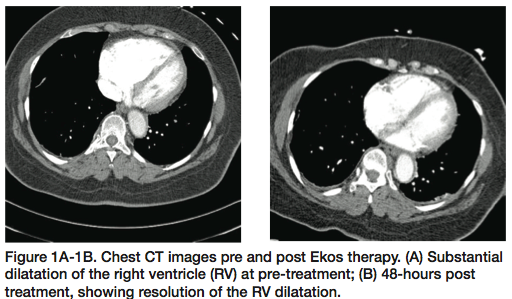

SEATTLE II began in June 2012 with the goal of 150 patients. Enrollment is going extremely well and over halfway at this point. The trial has two endpoints. First, efficacy: measuring the improvement in right ventricular/left ventricular ratio after use of the ultrasound-assisted thrombolysis catheter in submassive or massive pulmonary embolism (PE). Patients get a pre-treatment computed tomography angiography (CTA) of the chest, we perform the treatment, and then the patient undergoes a post treatment CTA of the chest 48 hours later. The second endpoint is safety: looking at the complications that may develop during treatment.

We also measure pulmonary artery pressures pre and post treatment. After we treat the patient, the PA pressure can be measured through the existing Ekos catheter with the patient in the ICU. We have seen a nice reduction in pulmonary hypertension. We are looking for a decrease in the right ventricular/left ventricular ratio within 48 hours ± 6 hours, along with a safety profile.